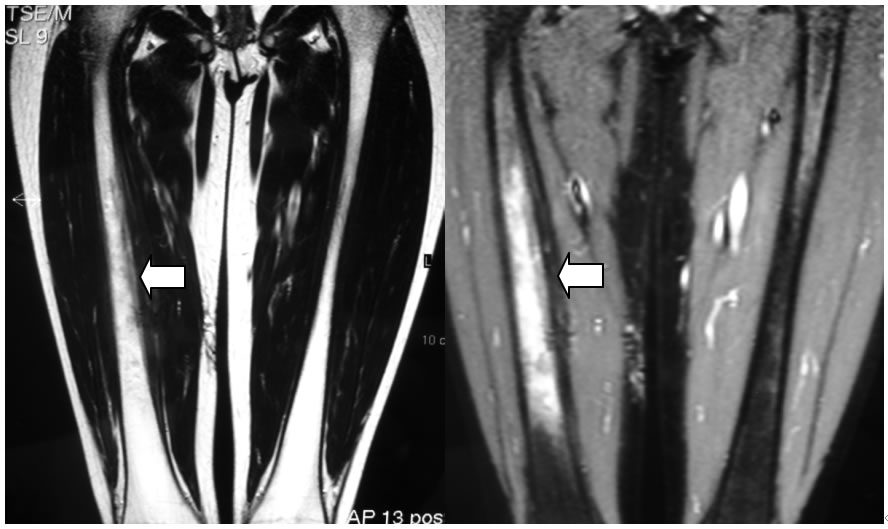

Visto il recidivare della sintomatologia a due anni dall'esordio, in una lesione monofocale, preoccu-pati comunque di poter perdere una diagnosi di tumore “prendiamo tempo” con l'esecuzione di una RMN (figura 3a, figura 3b),

Figure 3a, 3b: RM, piani coronali con mezzo di contrasto (T1) confermano il reperto e mostrano una marcata vascolarizzazione a tale livello.